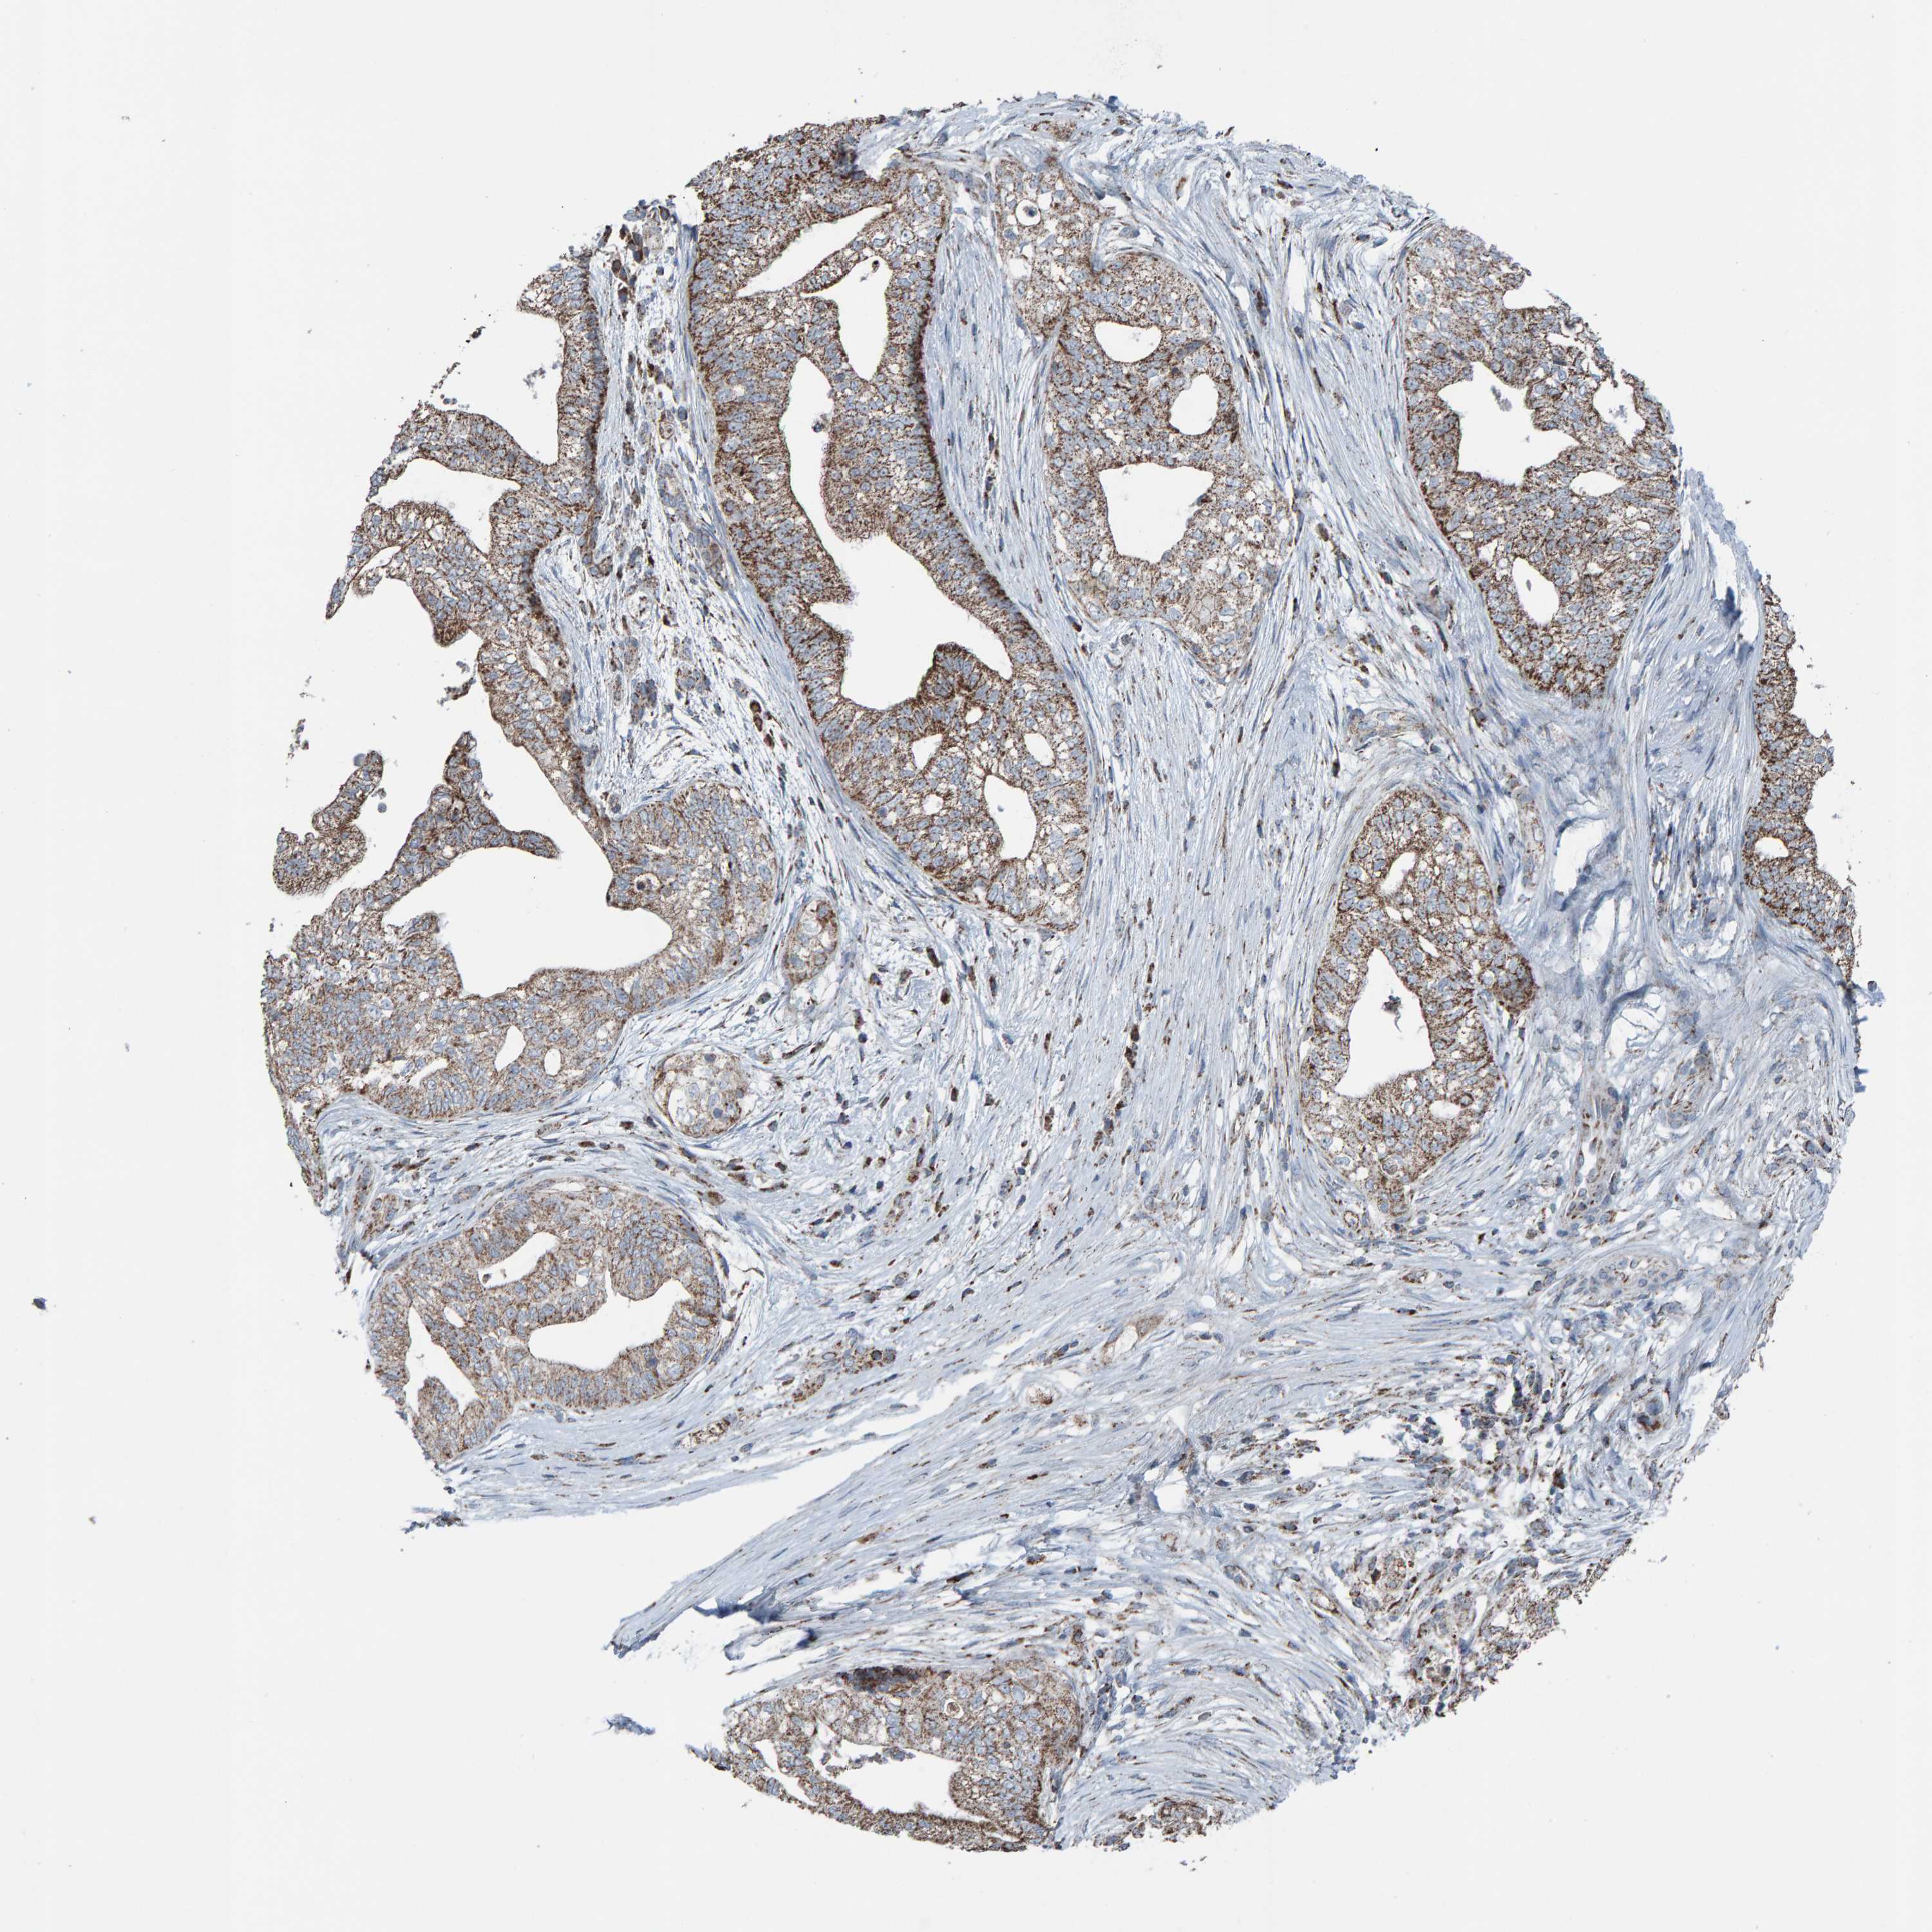

PANCREATIC CANCER - Protein expressioni

A mouse-over function shows sample information and annotation data. Click on an image to view it in a full screen mode. Samples can be filtered based on level of antibody staining by selecting one or several of the following categories: high, medium, low and not detected. The assay and annotation is described here.

Note that samples used for immunohistochemistry by the Human Protein Atlas do not correspond to samples in the TCGA dataset.

Antibody stainingi

Antibody staining in the annotated cell types in the current human tissue is reported as not detected, low, medium, or high, based on conventional immunohistochemistry profiling in selected tissues. This score is based on the combination of the staining intensity and fraction of stained cells.

Each image is clickable and will lead to virtual microscopy that enables deeper exploration of all samples and also displays staining intensity scores, fraction scores and subcellular localization as well as patient and tissue information for each sample.

Antibody HPA023806

Staining

High

Medium

Low

Not detected

Intensity

Strong

Moderate

Weak

Negative

Quantity

>75%

75%-25%

<25%

None

Location

Nuclear

Cytoplasmic/membranous

Cytoplasmic/membranous,nuclear

Adenocarcinoma, NOS